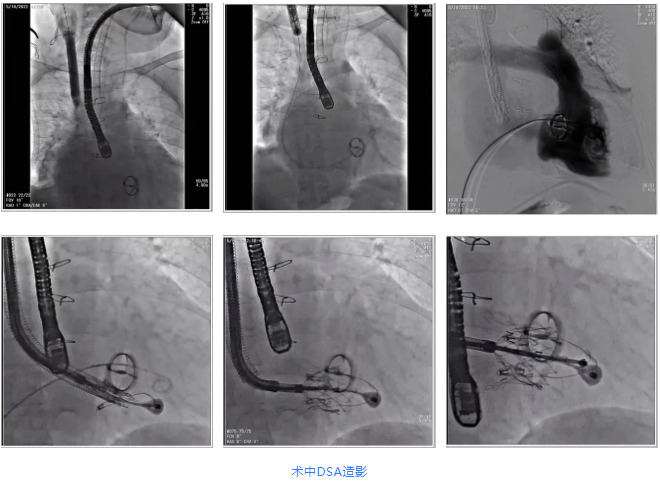

根據(jù)術(shù)前評(píng)估結(jié)果,郭應(yīng)強(qiáng)教授團(tuán)隊(duì)為患者量身定制了手術(shù)策略,決定使用LuX-Valve Plus經(jīng)血管三尖瓣置換系統(tǒng)開(kāi)展手術(shù)治療。手術(shù)在全麻下進(jìn)行,采用經(jīng)右側(cè)頸靜脈入路,在經(jīng)食道超聲和DSA的指引下調(diào)整輸送器角度以達(dá)到正確位置,勾住前瓣后逐步釋放盤片,盤片打開(kāi)后順利扎針,最終完成瓣膜植入,輸送器撤出。術(shù)后超聲提示人工三尖瓣同軸性良好,瓣架固定牢靠,無(wú)反流和瓣周漏,術(shù)后三尖瓣平均跨瓣壓差為1 mmHg。